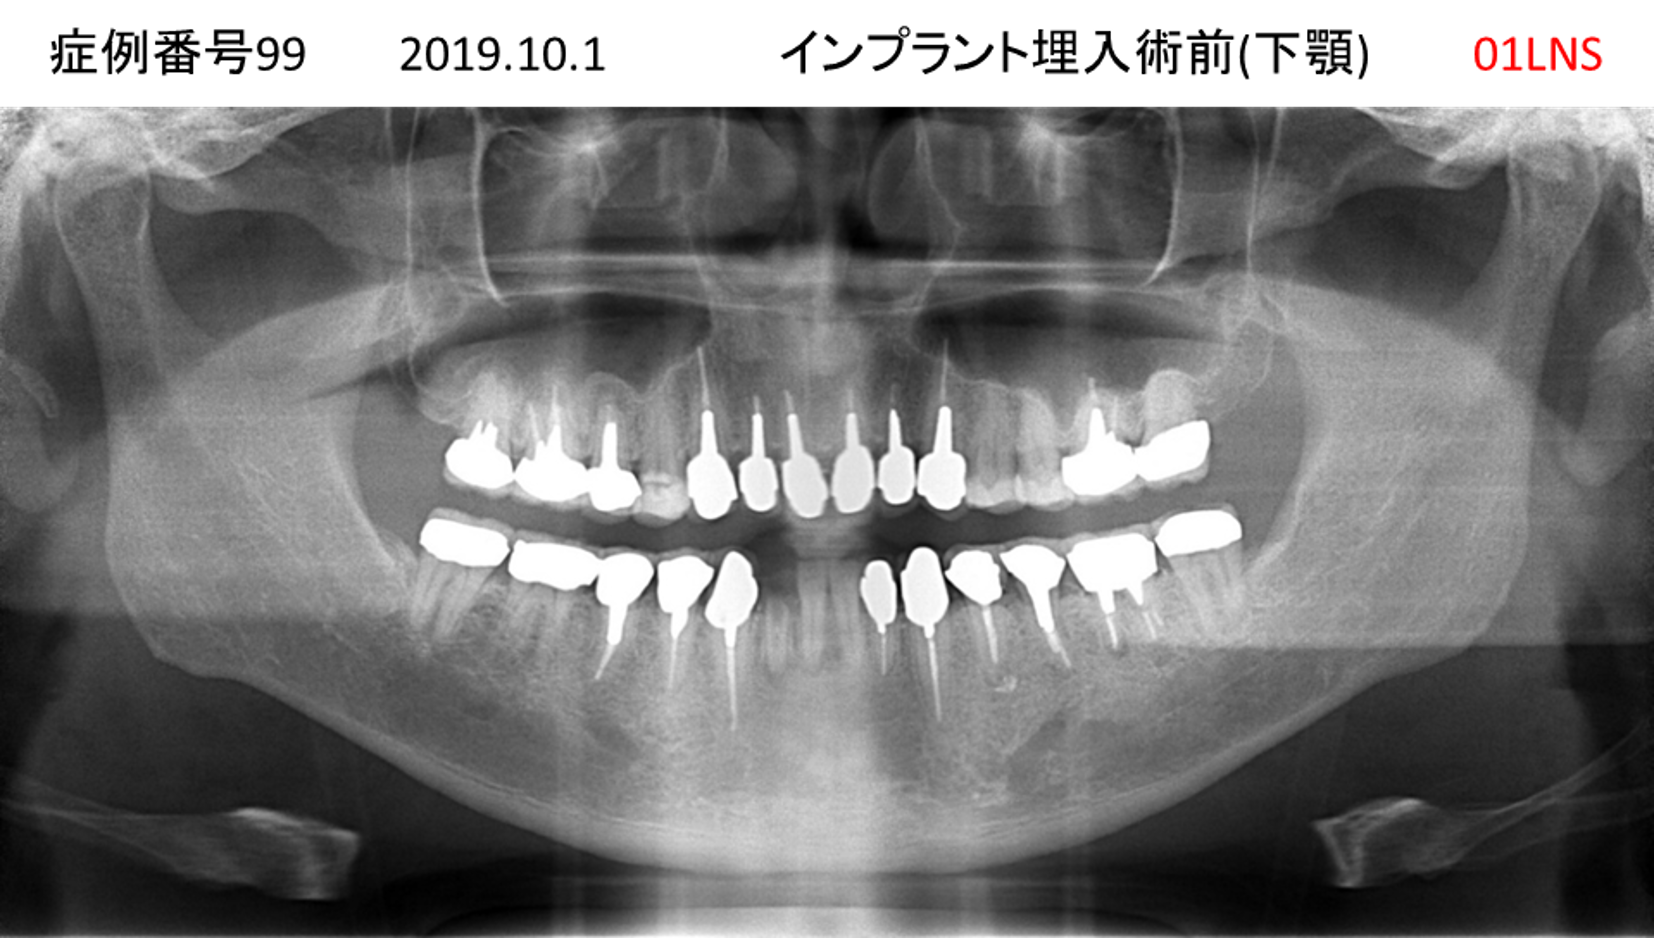

全く噛めない患者様のインプラント症例

| 治療名称 |

インプラントオーバーデンチャー |

| 治療費用 |

520万円+税 |

| 治療期間 |

6か月 |

| 患者さんの症状(主訴) |

全く噛めない。何とかしてほしい |

| 治療内容 |

サイナスリフト、インプラント、義歯作製(ロケーター) |

| 治療結果 |

好きなものが食べられるようになった。見栄えがとても良くなった。 |

| 治療の注意点(リスク/副作用) |

義歯が壊れた場合、インプラントが壊れた場合は再治療が必要 |